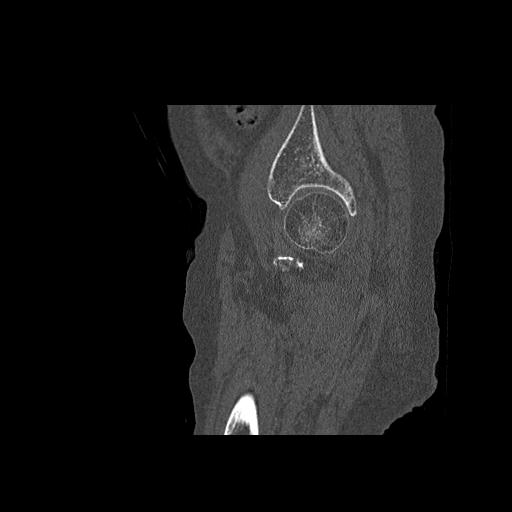

82084 1/14 1/20 股関節 2R 78歳男性 右人工骨頭